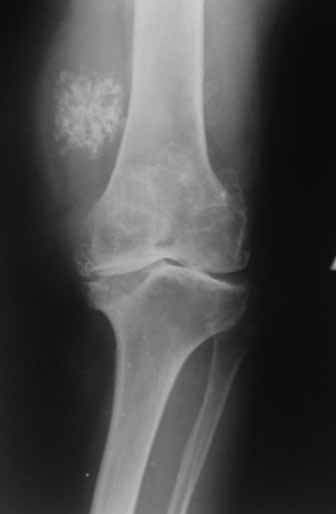

Пациентка 72 лет.Не обследовалась и не лечилась.

Работала поварихой до последнего времени.обратилась за медпомощью впервые.ходит без дополнительной опоры. Основные жалобы на ограничение движений и боли в правом коленном суставе.

Финансовые возможности ограничены.Чем можно помочь? Артродез? Протезирование?